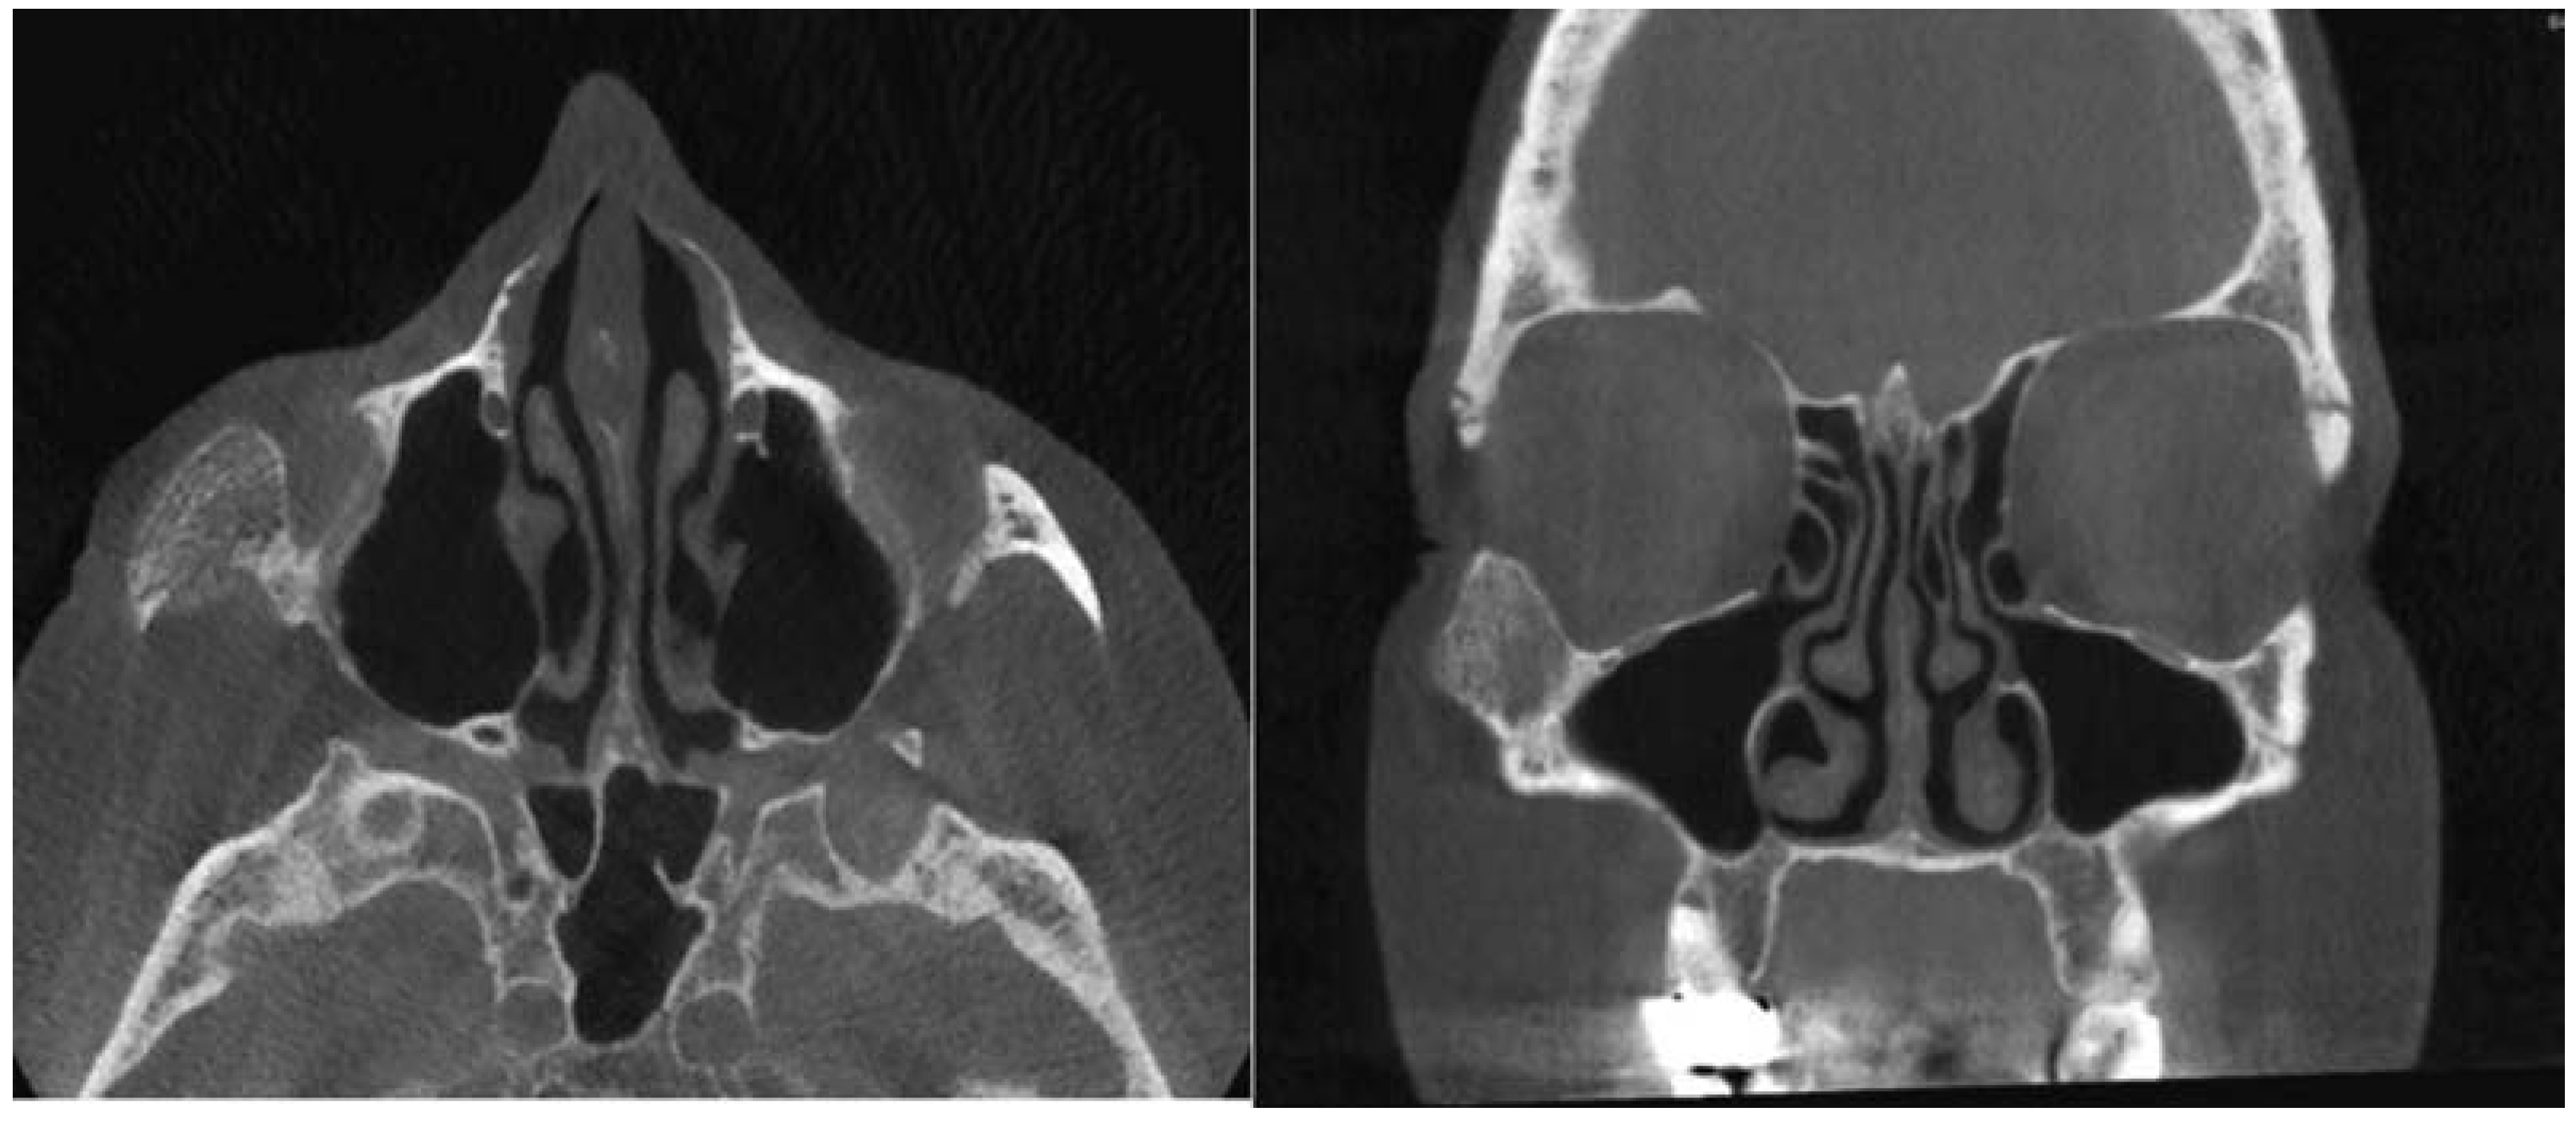

:Case Presentation

- Moore, S.L.; Chun, J.K.; Mitre, S.A.; Som, P.M. Intraosseous hemangioma of the zygoma: CT and MR findings. AJNR Am J Neuroradiol 2001, 22, 1383–1385. [Google Scholar] [PubMed]

- Razek, A.A. Imaging appearance of bone tumors of the maxillofacial region. World J Radiol 2011, 3, 125–134. [Google Scholar] [PubMed]

- Gonçalves, F.G.; Rojas, J.P.; Hanagandi, P.B.; et al. Case report: Periorbital intraosseous hemangiomas. Indian J Radiol Imaging 2011, 21, 287–290. [Google Scholar]